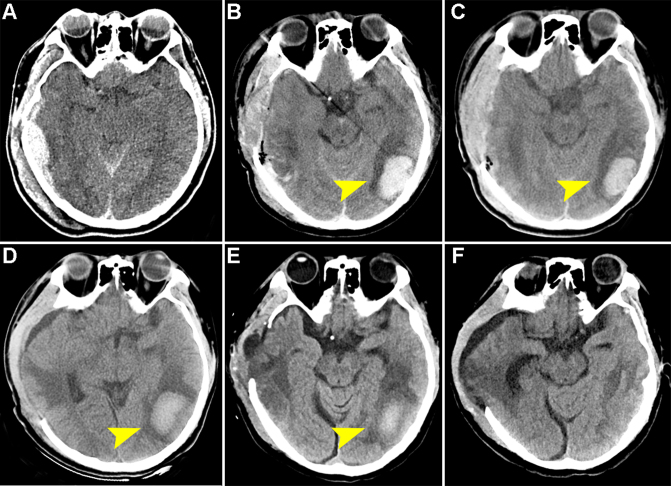

Observations: The authors conducted a retrospective case series analysis of 10 TBI cases admitted to their center between January 2021 and December 2023. These patients were airlifted from areas > 3500 m above sea level. On admission and at specified intervals up to 30 days postadmission, patients underwent head CT scans, laboratory tests, and posttraumatic stress disorder (PTSD) assessments. Self-care ability scores and psychological assessments were obtained at various time points postdischarge. With a precise and proactive treatment strategy, there was a significant reduction in intracranial hematoma volume, hemoglobin levels, D-dimer, procalcitonin, and serum sodium by the 30th day. The incidence of PTSD was markedly reduced at 6 months postdischarge compared with initial assessments within the 1st week.

Lessons: TBI patients transferred from high-altitude areas exhibited persistent intracerebral hematoma, elevated intracranial pressure, relative anemia, hypercoagulation, etc., and thus a precise and proactive treatment would benefit these patients. https://thejns.org/doi/10.3171/CASE24823.